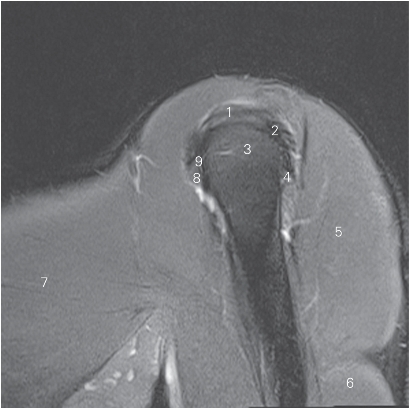

图4-18 经肱二头肌长头腱的矢状断层MR T2WI FS

1 冈上肌 supraspinatus 2 冈下肌 infraspinatus

3 肱骨头 head of humerus 4 小圆肌 teres minor

5 三角肌 deltoid 6 肱三头肌 triceps brachii

7 胸大肌 pectoralis major 8 小结节 lesser tubercle

9 肱二头肌长头腱 tendon of long head of biceps brachii

图4-19 经肩峰的矢状断层MR T2WI FS